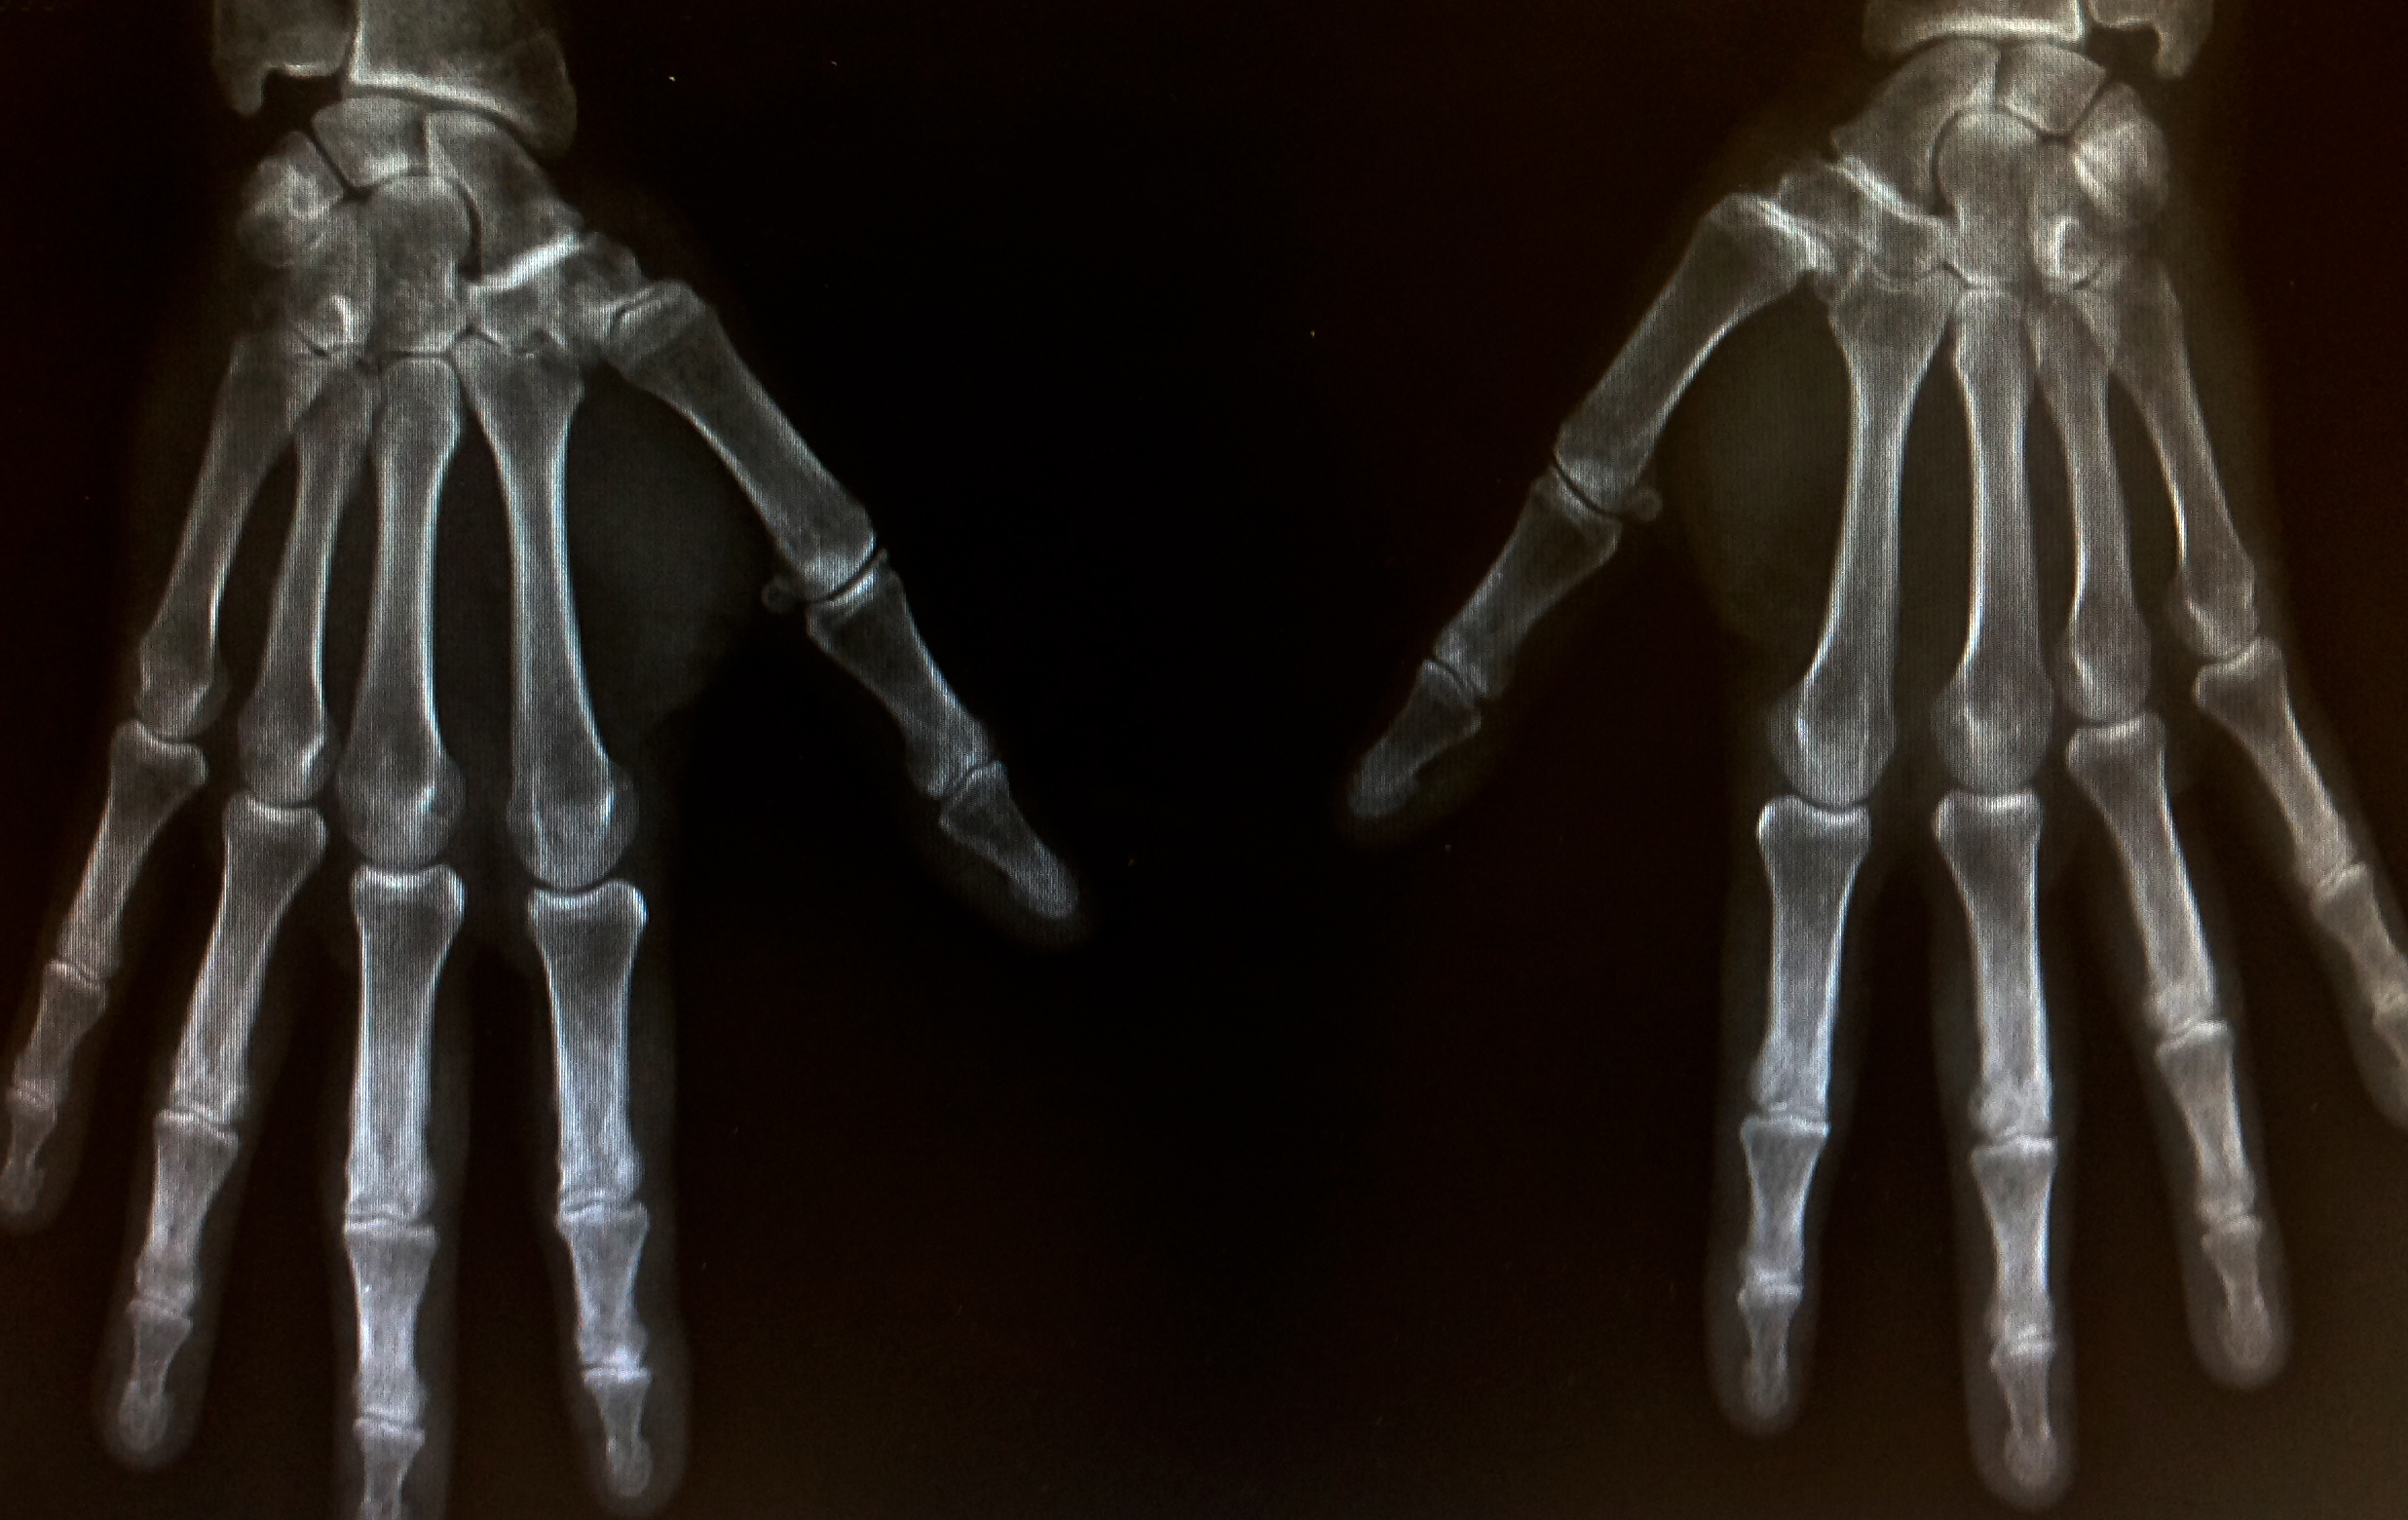

Rizartrosis, la artrosis del pulgar

El desgaste de la articulación que une el dedo pulgar de la mano con la muñeca da lugar a la rizartrosis o artrosis del pulgar, frecuente en los mayores de 65 años.

La articulación trapeciometacarpiana, la cual se encuentra en el dedo pulgar y le une con la muñeca, la degeneración articular en esta zona surge entre la base del primer metacarpiano y el hueso trapecio de la muñeca, y es lo que se conoce como rizartrosis. El hecho de que la rizartrosis surja en las manos conlleva que repercuta negativamente en muchas de nuestras tareas cotidianas. Esta enfermedad reumática reduce la calidad de vida de la persona que la padece. Con el fin de evitar que la degeneración siga avanzando es importante acudir al médico ante estos síntomas de alerta de la artrosis del pulgar: Dolor en la base del dedo pulgar (es el primer síntoma que surge y el más significativo. Puede aparecer solo en una mano, o en las dos, y se acentúa cuanto más se utiliza la articulación, mientras que se reduce cuando se mantiene en reposo).